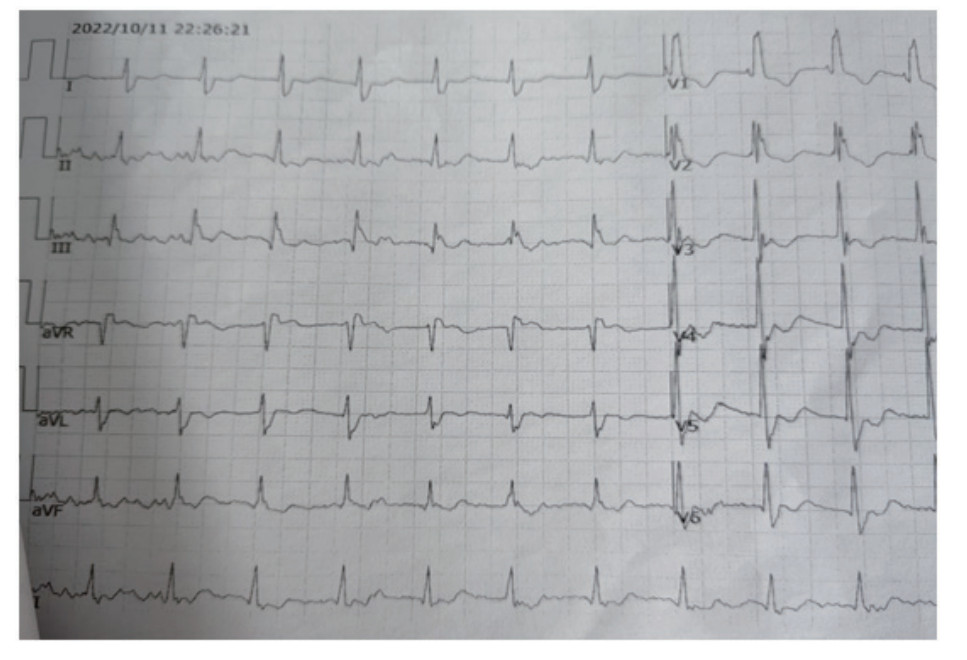

1 资料与方法患者,男性,59岁,2022年10月11日21:42:26,九江市医疗急救中心调度员接到报警电话,家住某小区患者猝然倒地,意识不清, 呼之不应。21:43:02调度员派出救护车,同时启用ADLS,并应用ADLS中的CPR预案判断现场环境安全和确定患者为心脏骤停后,立即安抚报警人情绪,让其遵从120调度员的在线指导,将患者放于地面上,跪于患者右侧,双手交叠置于两乳头连线的正中间,始终保持手肘伸直,用手掌根部快速用力向下按压5~6 cm, 并通过ADLS中的计数工具指导报警人按压的频率,指导界面见图 1。21:54:02(接警后11分36秒)救护车到达现场接替报警人,并开始实施高级生命支持,急救人员建立静脉通路,静脉推注肾上腺素并持续心肺复苏术。22:03:29院前首份心电图提示心室颤动(图 2),急救人员立即进行除颤200 J;22:07:04心电监护仍提示为室颤,急救人员进行第二次除颤200 J,22:26:21现场心电图转为窦性心律(图 3),急救人员现场复苏成功,恢复患者自主循环, 口唇由发绀转为红润,瞳孔由大变小(直径由6 mm缩小为3 mm),遂将患者以“心脏骤停复苏成功、心源性休克”立即送往院内进一步诊治。患者既往两次脑梗死病史、高血压病史,个人史、过敏史、家族史无特殊。

| 图 3 患者现场除颤后心电图示窦性心律 |